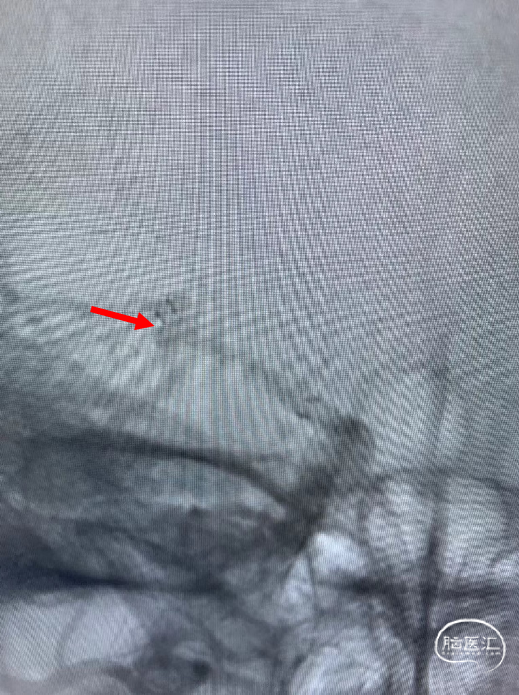

支架微导管到位后,释放支架。

支架释放后,送入首枚2*4的弹簧圈栓塞动脉瘤。